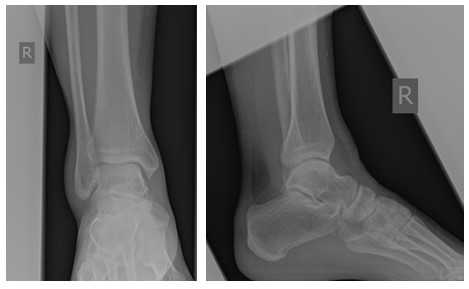

Пациент Ч. 23 года, травма во время игры в футбол, подвернул правую стопу кнаружи при резком толчке, услышал хруст, почувствовал резкую боль. Обратился в травмпункт, где выполнены рентгенограммы без нагрузки, рекомендована иммобилизация в ортезной повязке 2 недели и консервативное лечение. Учитывая отсутствие положительной динамики, принял решение обратиться на консультацию в клинику К+31.

В нашей клинике пациент Ч. Был осмотрен врачом, заподозрено повреждение дистального межберцового синдесмоза, на фоне хронической нестабильнсоти голеностопного сустава. Были выполнены МРТ голеностопного сустава и рентгенография голеностопных суставов стоя с нагрузкой весом тела, а также стресс-рентгенограммы, в вынужденном положении, которые подтвердили диагноз.

Очень важно чтобы при первичном обращении в травмпункт, пациентам с повреждением связочного аппарата голеностопного сустава производились полноценные рентгенограммы, стоя с нагрузкой весом тела, косая проекция с внутренней ротацией голени 15 градусов, а при необходимости, и стресс-рентгенограммы.

При детальном изучении снимков определяется увеличение межберцовой щели до 7,5 мм, уменьшения зоны перекрытия большеберцовой и малоберцовой костей до 5 мм, отсутствие на стороне поражения перекрытия тени таранной кости и малоберцовой кости.

На рентгенограмме костей правого и левого голеностопных суставов в прямой проекциии, снимки стоя - справа определяются признаки повреждения дистального межберцового синдесмоза - степень взаимного перекрытия берцовых костей 5мм (в норме больше 6мм) увеличенное большеберцовое - малоберцовое пространство - 7.5мм (в норме до 6мм).